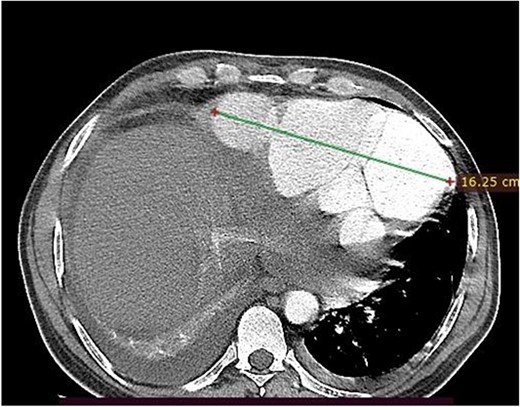

A 46-year-old man from rural Ethiopia was referred 7 days after he started to have sudden shortness of breath, chest pain and cough. On 6th day of his symptoms, he had brief loss of consciousness and left-sided body weakness. When he arrived to our hospital on 7th day of symptom onset, his vitals were: blood pressure 100/70 mmHg, pulse rate 104–112 beat/min, respiratory rate 24 breaths/min, SpO2 95% on room air. There was Grade 3 systolic murmur at the apex. Power of left upper and lower extremities was 3 and 4 out of 5, respectively. Laboratory tests were white cell count of 15 800, with 89% neutrophils, hemoglobin of 11.4 g/dl, platelet count of 180 000, INR of 2.2. Cardiac markers and Electrocardiogram (ECG) were normal. Echocardiography showed 19 mm defect at apex of left ventricle with bidirectional flow between ventricular chamber and pseudoaneurysmal septated intrapericardial collection. Chest CT revealed huge pseudoaneurysm (contained rupture) the communicates with left ventricle via a 2.1 cm rupture (see Figs 1 and 2). Patient’s medical history was relevant for unprovoked deep venous thrombosis (DVT) of left lower extremity a year back, which was treated with warfarin.

Axial image, just below the lower level of the heart, shows a 16 cm septated pseudoaneurysm that enhances with contrast.

With diagnosis of embolic stroke and LV pseudoaneurysm, he was stabilized in cardiac intensive care unit, and then operated via median sternotomy. Pericardium appeared edematous and darkened because of underlying hematomata. To prevent uncontrolled bleeding, extrapericardial cannulation was done on ascending aorta. Then pericardium covering right atrium was then opened and superior vena cava was cannulated and bypass was initiated. When pericardium over the pseudoaneurysm was then opened, there was a huge cavity measuring about 16 cm transverse and 10 cm vertically, which had pushed the heart upward. There was some thrombus inside. It was freely communicating with inferior wall of LV close to apex through a 2 cm rupture. The cavity wall and coagulated hematoma were removed and perforation repaired with Dacron patch (see Fig. 3). Chest tube and mediastinal tube were left and sternum was closed. He had smooth postoperative course with normal postoperative echocardiography. He stayed for 12 days in the ICU and was discharged on 18th postoperative day. He did not require any cardiac medications.